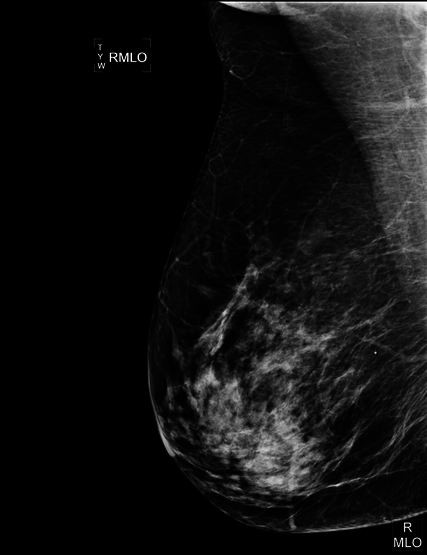

Mamografia digitalizada

A Bio Imagem oferece um dos recentes avanços da mamografia, a Mamografia Digitalizada.

Se assemelha a convencional por usar raios X na produção das imagens porém o sistema é equipado com um receptor digital, o qual converte a imagem numa foto digital e pode ser revisado no monitor do computador, podendo ser alterados orientação, brilho e contraste, visando perceber diferentes áreas da mama.